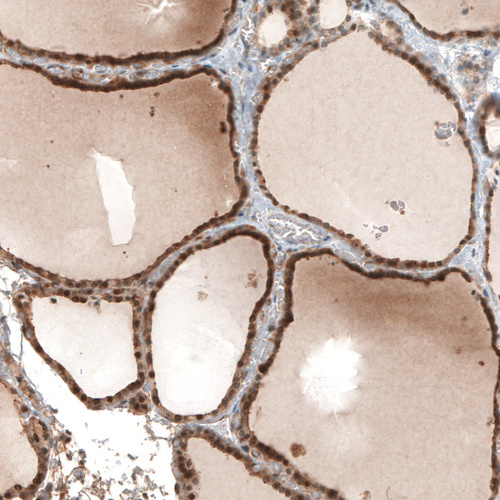

Immunohistochemical staining of human thyroid gland shows moderate cytoplasmic positivity in glandular cells.